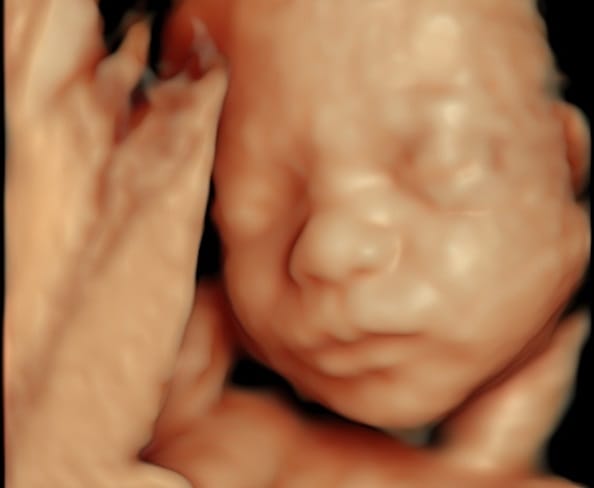

![[Ads] Ultrasound Baby Scan 7 new](https://klinikazurose.com/wp-content/uploads/2025/03/new.jpg)

See your baby like never before with the 3D, and 4D Scan between 24 and 32 weeks. This session includes a 3D Colour Scan, a Growth Scan, and a Gender Scan. You’ll also receive photos and a video.